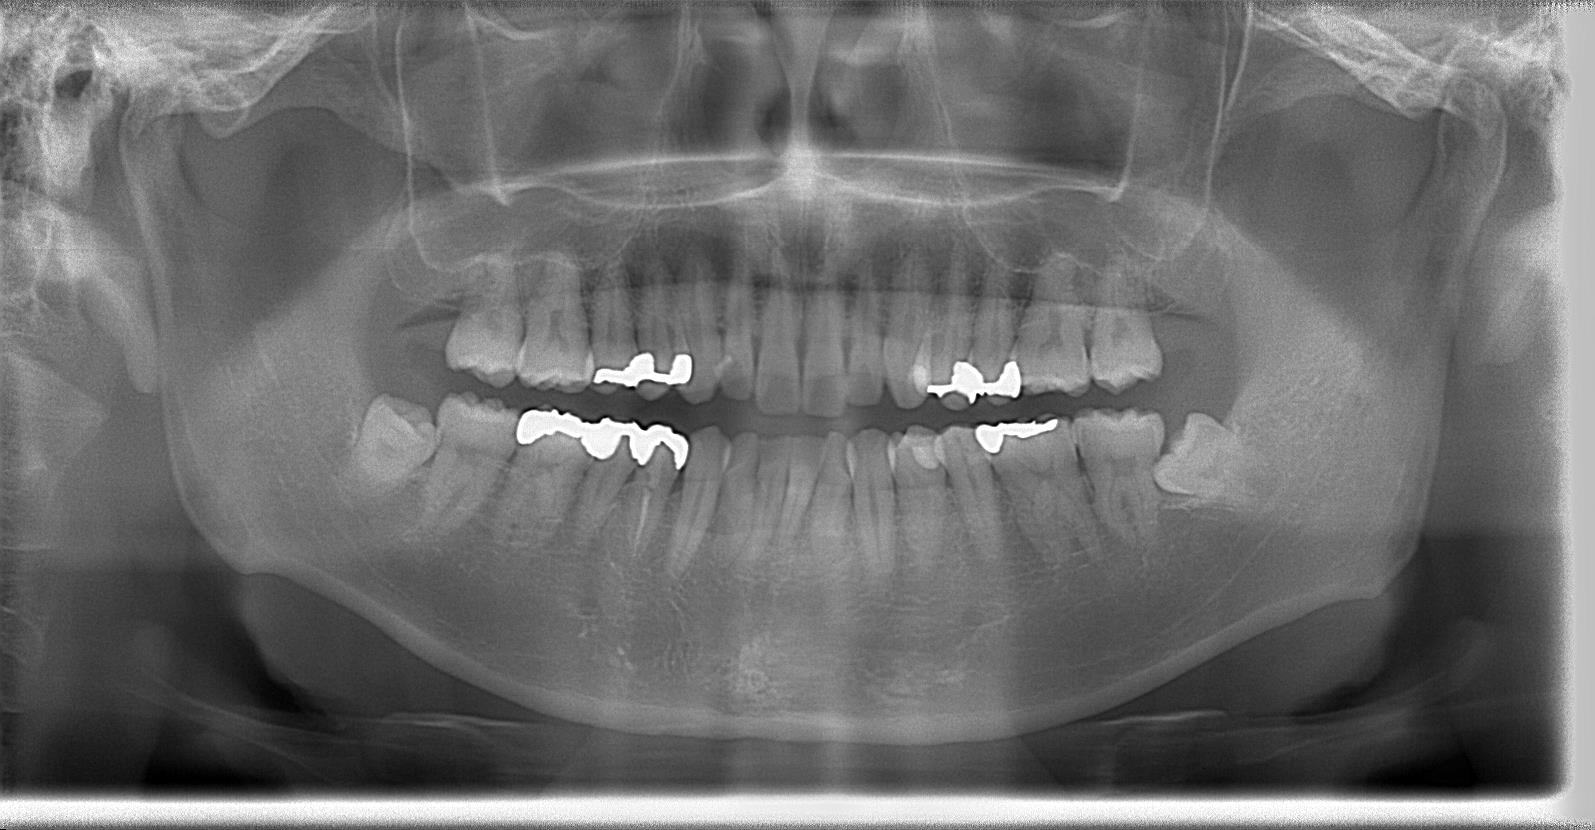

パノラマレントゲン写真